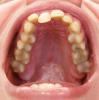

Repby Опубликовано 5 января, 2011 Поделиться Опубликовано 5 января, 2011 Здравствуйте!Мне 37 лет. Прошу помочь определиться с тактикой лечения:1) Какую брекет-систему использовать? Имеет ли преимущество система Damon в моем случае?2) Есть ли возможность провести лечение без удаления зубов?3) Единственная 8-ка снизу слева - ее удаление планируется по терапевтическим показаниям. Это поможет исправлению нижней челюсти?Спасибо. Ссылка на комментарий